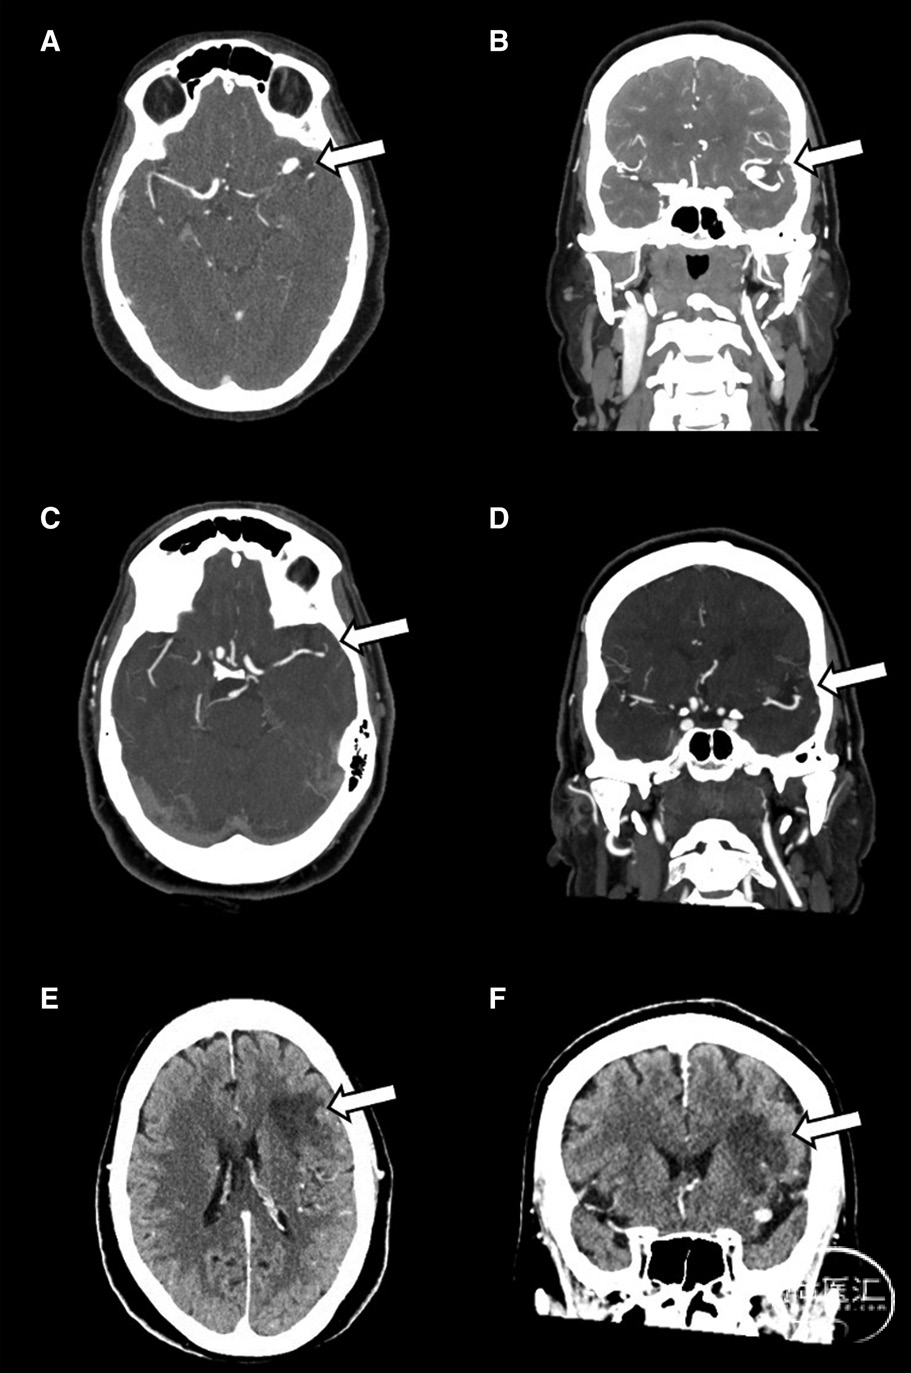

CTA(图2)显示左侧M2分叉处囊性动脉瘤。图A和B,动脉瘤内高信号(造影剂)。图C和D,血栓形成后动脉瘤内低信号。图E和F,左侧M2上干梗死: